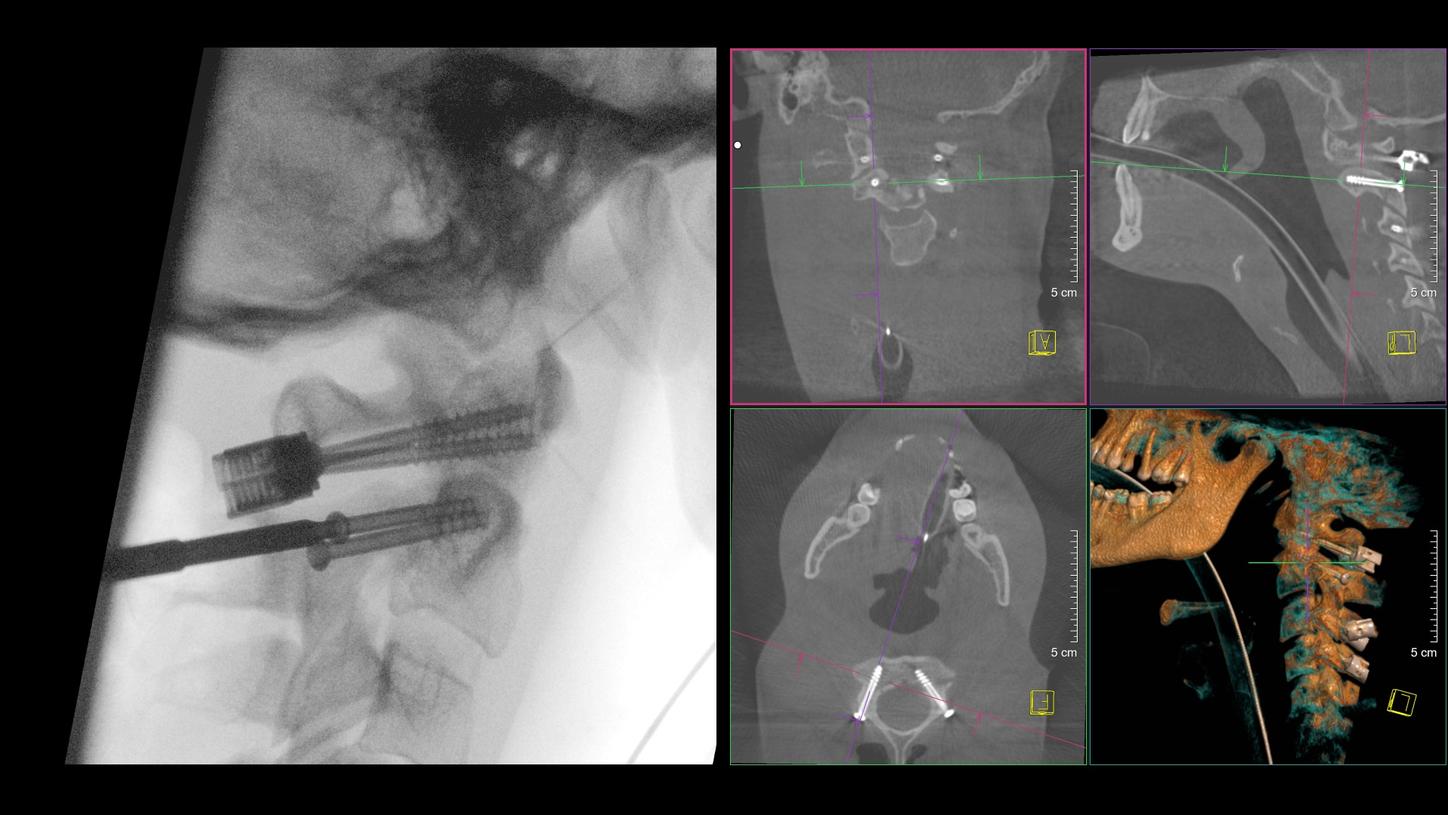

With Smart Control, a single person can operate the system remotely. The wireless Smart Control allows you to do so even from inside the sterile field.1

NaviLink 3D2

3D volume for image-based registration of navigation markers

25 x 25 x 16 cm (10’’ x 10’’ x 6.3’’); resolution: 800 x 800 x 512 voxels